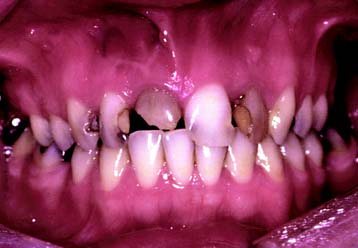

Compromised appearance is a strong motivating factor for patients to seek advice as to whether improvement is possible (Fig. 1-3). Such patients may have missing or crowded teeth, or a tooth or restoration may be fractured. Their teeth may be unattractively shaped, malpositioned, or discolored, or there may be a developmental defect.

This class (Figs. 1-27 and 1-28) is characterized by ideal or minimal compromise in the location and extent of edentulous area (which is confined to a single arch), abutment conditions, occlusal characteristics, and residual ridge conditions. All four of the diagnostic criteria are favorable.

This class (Figs. 1-33 and 1-34) is characterized by severely compromised location and extent of edentulous areas with guarded prognosis, abutments requiring extensive therapy, occlusion characteristics necessitating reestablishment of the occlusion with a change in the occlusal vertical dimension, and residual ridge conditions.

Fig. 1-33 Class IV patient. Edentulous areas are found in both arches, and the physiologic abutment support is compromised. Abutment condition is severely compromised as a result of advanced attrition and failing restorations, necessitating extracoronal restorations and adjunctive therapy. The occlusion is severely compromised, necessitating reestablishment of occlusal vertical dimension and proper occlusal scheme. A, Frontal view, maximum intercuspation. B, Right lateral view, maximum intercuspation. C, Left lateral view, maximum intercuspation. D, Occlusal view, maxillary arch. E, Occlusal view, mandibular arch. F, Frontal view, protrusive relationship. G, Right lateral view, right working movement. H, Left lateral view, left working movement. I, Full-mouth radiographic series.